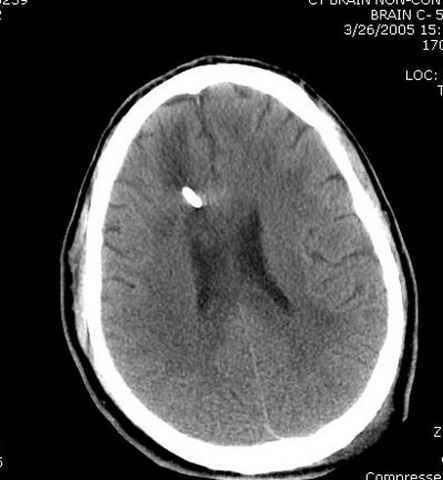

Наблюдается службой травмы и нейрохирургии (ICP) Increased Intracranial Pressure by ventricular cateter

больной без сознания, со слов нейрохирурга, наблюдается положительная динамика в нейрохирургическом статусе.

постоперационные

монииторинг

-Согласен, рана до прихода пластического хирурга была 38х13 см, можно было постараться закрыть сверху, а в нижнем отделе где был ожог, применить кожную пластику меньшим размером. К моему удивлению и разочарованию, когда вернулся из другой операционной (шли пареллельные операции), он уже успешно заканчивал свое дело. Кстати недавно разговаривал с нейрохирургом, он снял ICP (intracranial prеssure monitor), внутричерепное давление стабилизировалось, ортопеды и хирурги закончили с лечением, теперь длительное неврологическое восстановление.